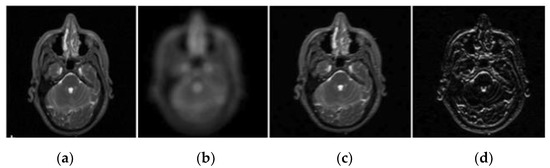

2.1. Pre-Processing

2.2. Wavelet Decomposition